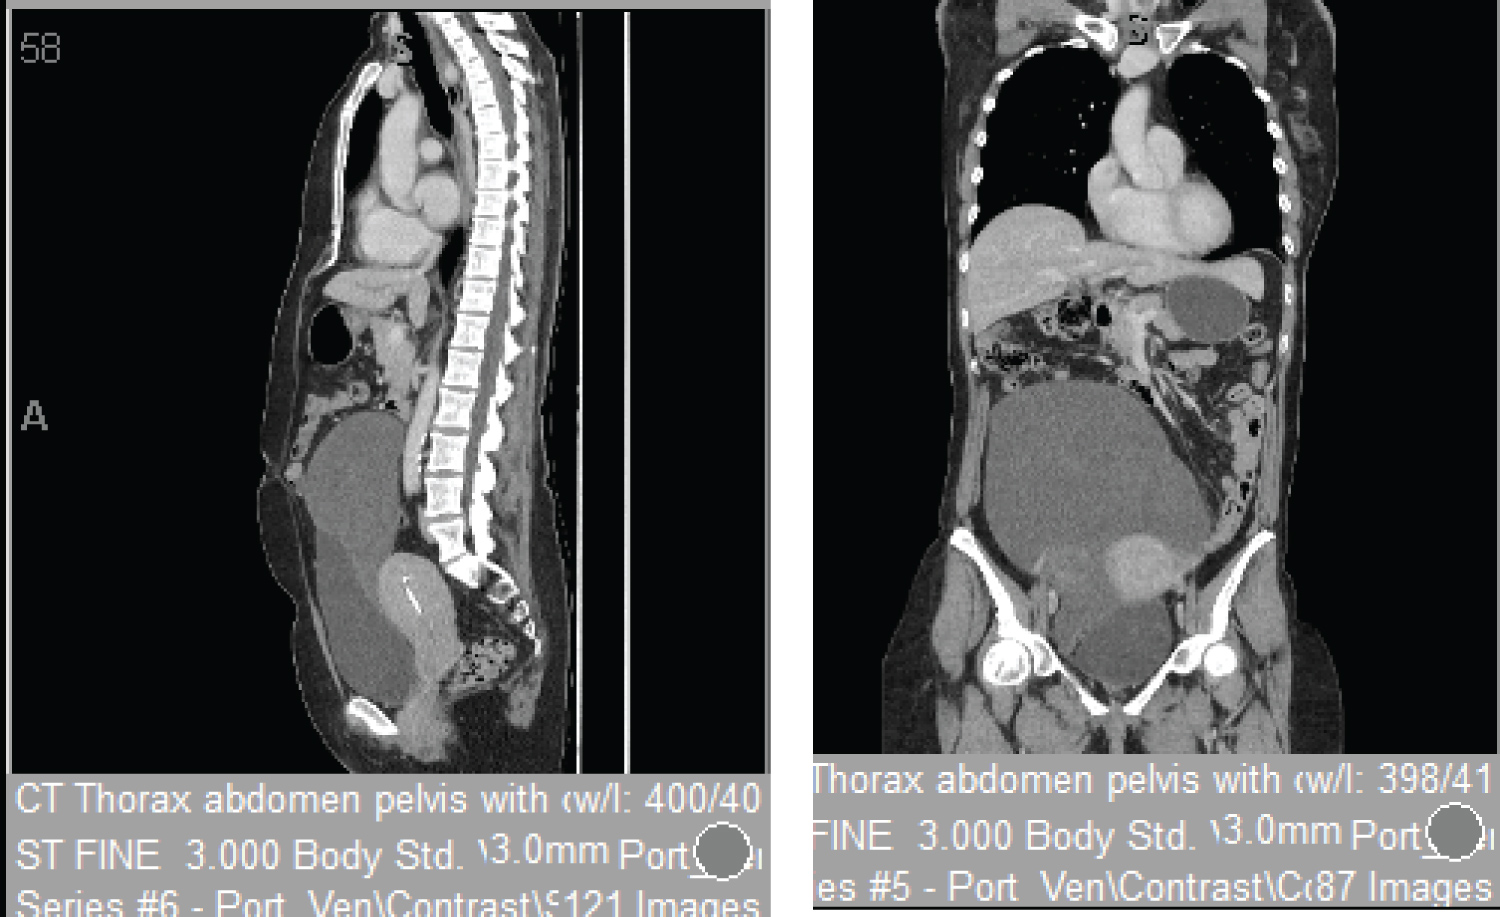

Imaging studies were performed. A CT thorax abdomen and pelvis revealed a large complex cystic mass filling the central and right pelvis and extending to above the level of umbilicus. It was suspected to be of ovarian origin due to the age of the patient, location, size and cystic nature of the mass (Figure 1).

Figure 1: CT thorax abdomen and pelvis revealed a large complex cystic mass filling the central and right pelvis and extending to above the level of umbilicus. View Figure 1